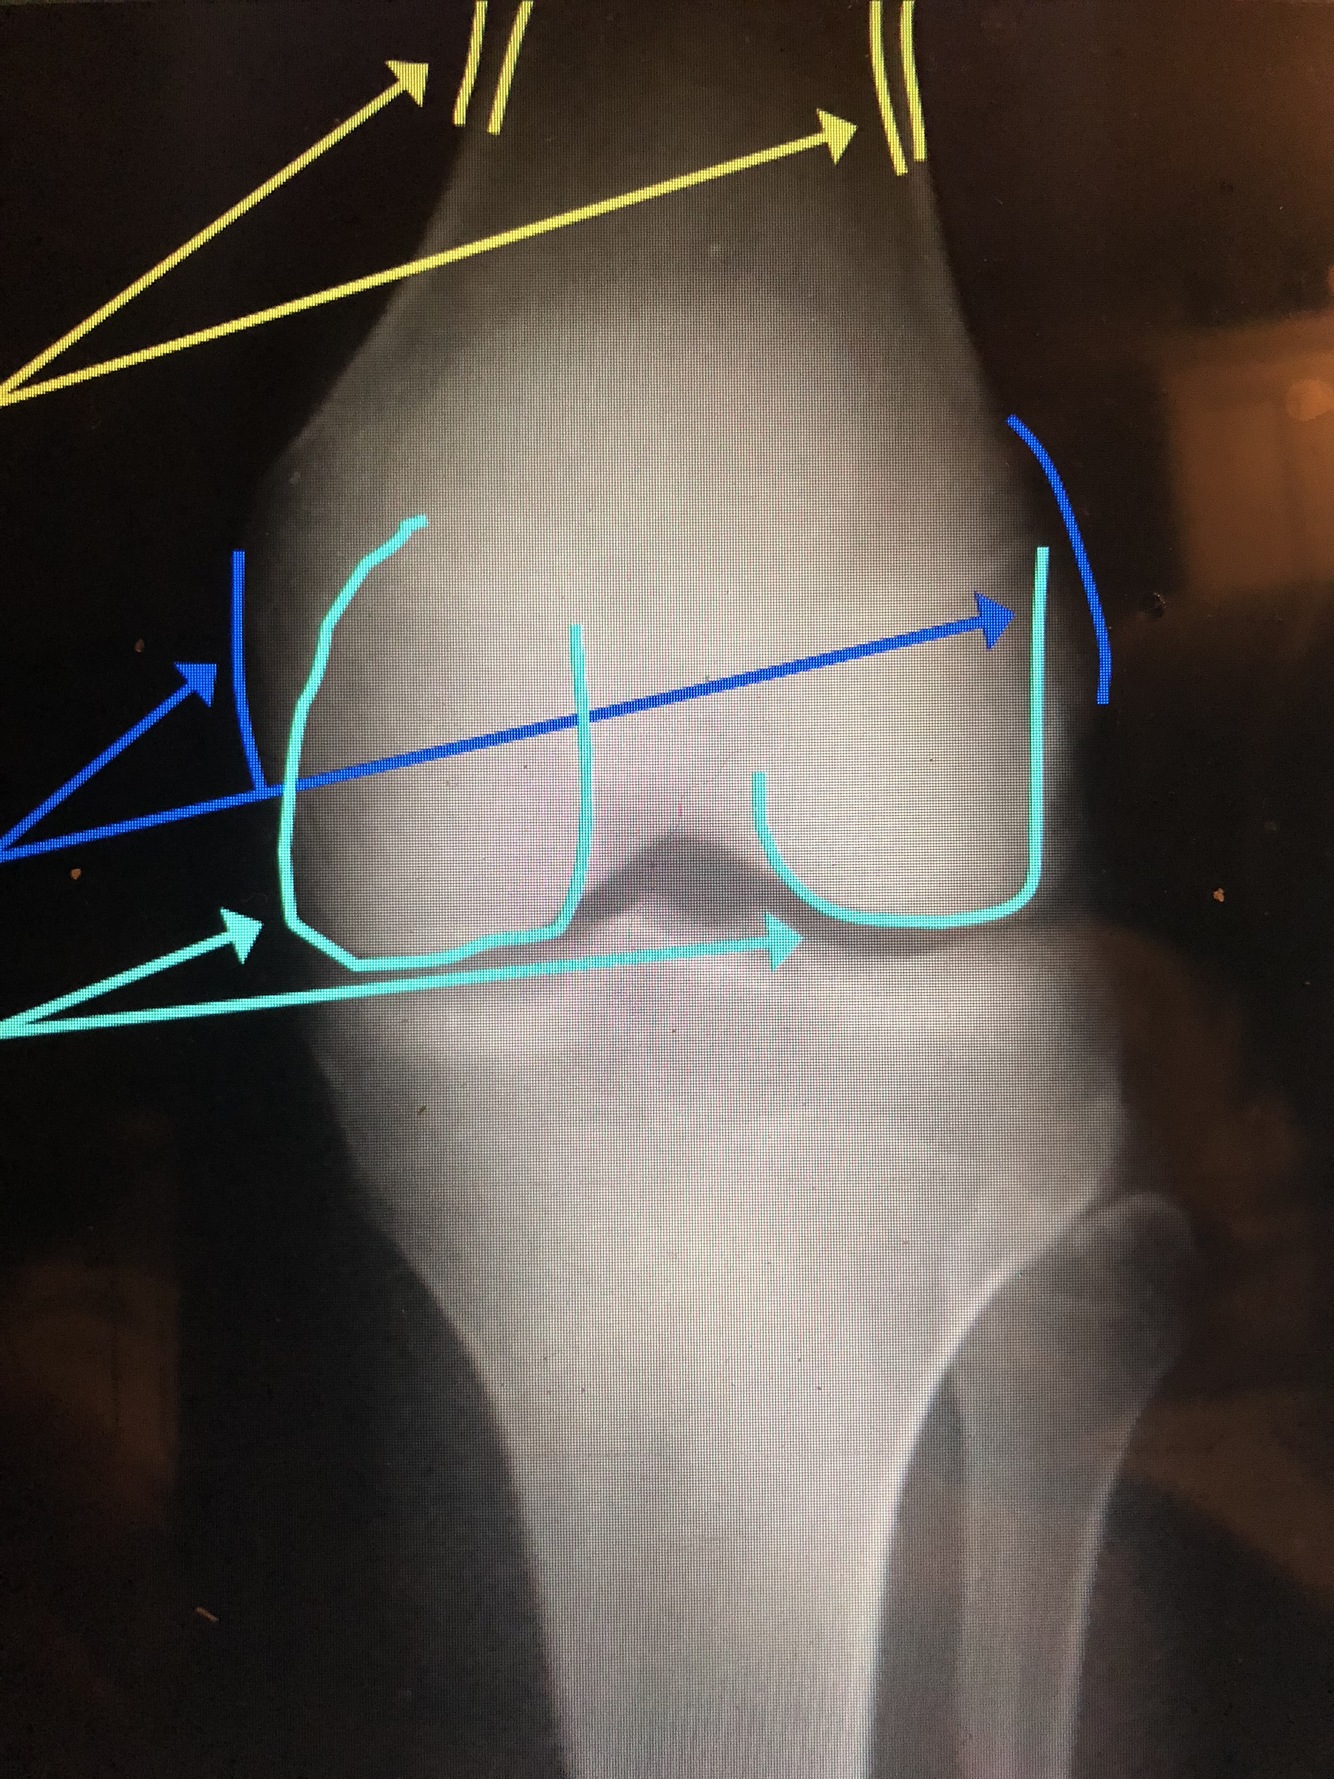

Q

Epicondyles (med. & lat.)

Femoral Condyles (med. & lat.)

What are the yellow lines?

Supracondylar Ridge/Line (med. & lat.)

What is the light blue line?

Medial Tibial Condyle

26

Superior Pole (Base) of the Patella

Medial Intercondylar Spine/Eminence

What is the yellow line?

Lateral Intercondylar Spine/Eminence – is usually larger and more anteriorly located

What is the dotted white line?

Tibial Physeal Scar/Line